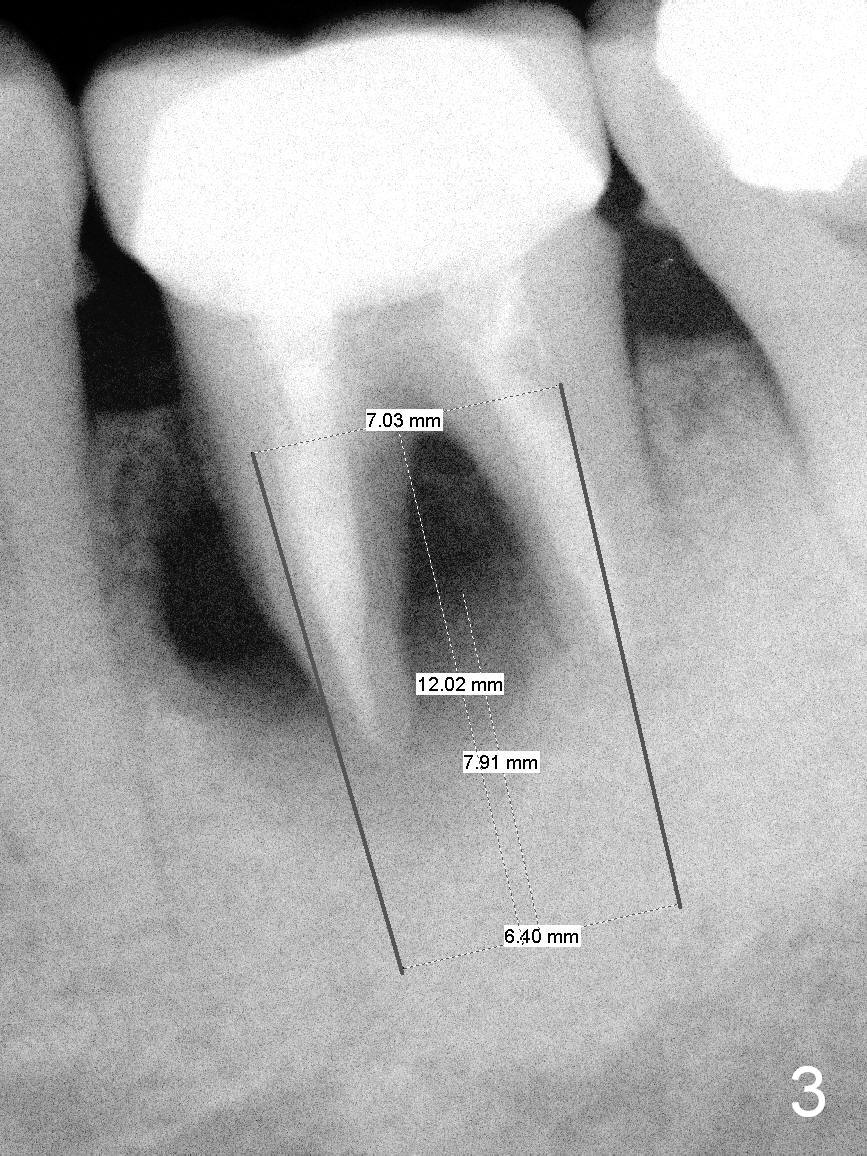

The tooth #19 of a 54-year-old man (FJ) looked normal 2.5 years ago (Fig.1).  The patient returns because of 3 fistulae developing around the mesial root of the tooth.  Recent PA shows a large radiaolucent defect (Fig.2,3).  To place an implant in the middle of the edentulous space, initial osteotomy should be distal because of the large mesial defect.